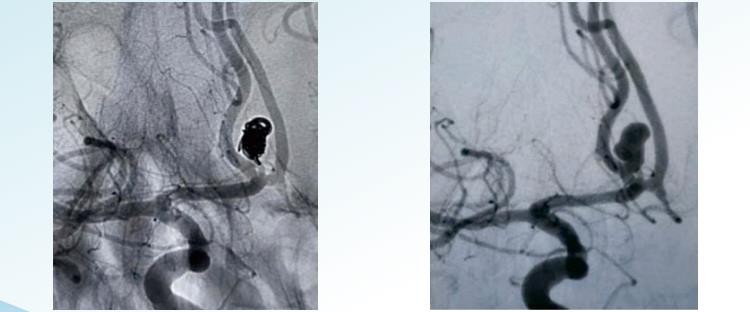

RenovaTMA levehető aneurizma tekercselő rendszer véletlenszerű, spirális és 3D-s leválasztható lehetőségeket kínál az endovaszkuláris embolizációhoz 1-22 m átmérőben. Úgy tervezték, hogy embolizálja az aneurizmákat a kerettől a végéig, és speciálisan a koncentrikus aneurizma kitöltésére kialakított tekercseket és nagy térfogatú tekercseket tartalmaz a nagy tömörítési sűrűség eléréséhez. A véletlenszerű tekercselés az aneurizma tekercselési technikájának legegyszerűbb és legrégebbi formája. Ez magában foglalja egyetlen tekercs vagy tekercscsoport behelyezését az aneurizmába. A tekercsek általában platinából készülnek, vékonyak és szorosan feltekerednek, hogy megakadályozzák hézagok vagy hézagok kialakulását a tasakban. A spirális tekercselés egy hosszabb, vékony huzal használatát foglalja magában, amelyet spirálisan tekernek maga köré, és rugószerű szerkezetet alkotnak. A drótot kiegyenesített formában behelyezzük az aneurizmába, és miután bekerült, hagyjuk feltekerni és kitágulni, hogy kitöltse az aneurizmazsákot. A spirális tekercsek szélesebbek és szorosabbak, mint a véletlenszerű tekercsek, így jobb az aneurizma elzáródása. A 3D tekercs egy egyedi tervezésű{13}}tekercset használ, amelyet számítógépes képalkotó eljárással készítenek, amely az aneurizma pontos háromdimenziós modelljét hozza létre. A tekercset úgy gyártják, hogy megfeleljen az aneurizma pontos méretének és alakjának. Ezt a spiráltípust úgy tervezték, hogy szorosan illeszkedjen az aneurizmazsákba, kiváló elzáródást biztosítva és csökkenti a szövődmények kockázatát. 3A D tekercsek különösen hatékonyak a nehezen elérhető vagy törékeny erekben lévő aneurizmák kezelésében.

RenovaTM3D levehető tekercsek

RenovaTMHelikális levehető tekercsek